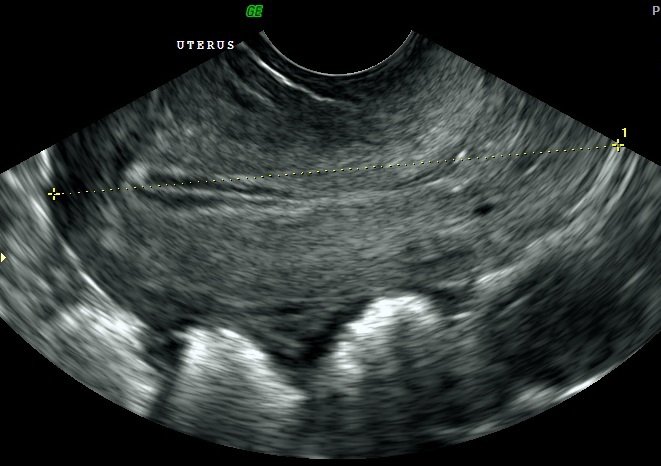

Performed to examine the uterus (womb) and ovaries, their size, shape and appearance. The lining of the womb (endometrium) is examined to check thickness as it can detect causes of bleeding in pre and post-menopausal women. It can also show reason of low abdominal pain and excess bleeding or intermitent bleeding. Also to check if you are missing your periods. scan pelvic uterus bood test

ENDOMETRIAL THICKNESS.

The Pelvic scans for Endometrial thickness can be arranged with us if your are about to undergo fertility treatment either within the Uk Or with a fertility clinic abroad. You can also request these scans independently to see if you are producing follicles and ovulating. A transvaginal ultrasound examination focussing on the endometrium (lining of the womb) with a basic assessment of the ovaries.

This scan will determine the thickness and appearance of the endometrium and the ovaries will be checked to ensure they do not have any large cysts within them.